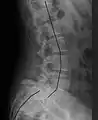

X-ray of measurement of spondylolisthesis at the lumbosacral joint, being 25% in this example

Classification by degree of the slippage, as measured as percentage of the width of the vertebral body:[17] Grade I spondylolisthesis accounts for approximately 75% of all cases.[7]

- Grade I: 0–25%

- Grade II: 25–50%

- Grade III: 50–75%

- Grade IV: 75–100%

- Grade V: greater than 100%